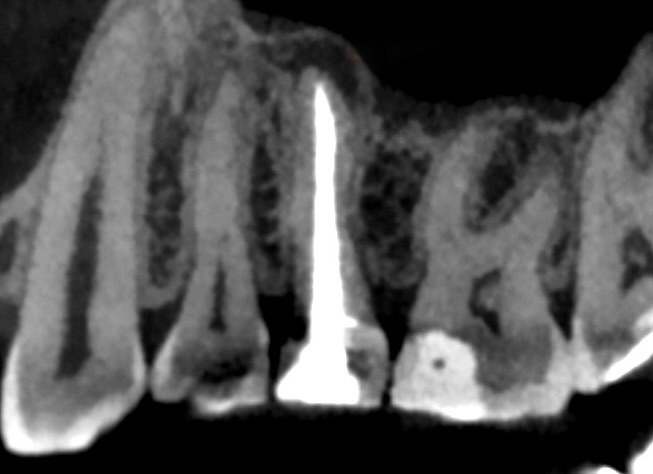

КТ до, периодонт

Распломбировали канал. На снимке рентгенологическом (КТ) был виден один, но что-то в анатомии настораживало. Роман Юрьевич подозревал два канала. Намёк на раздвоение был, но неубедительный. Рентген ничего не прояснил, КТ со стороны выглядела прилично, контрастный материал засвечивал всё вокруг.

На КТ этого не видно - контрастный материал засвечивал нужную область. Фотоаппарат - тем более не справился. Показал микроскоп на максимальном увеличении, в последних миллиметрах корня, там, где всё казалось давно изученным и увиденным.